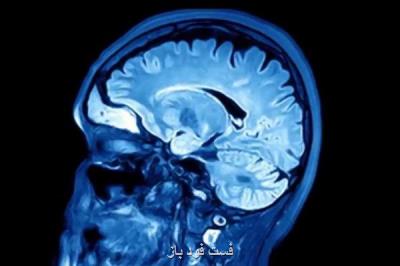

به گزارش فست فود باز به نقل از ایسنا، محققان آمریکایی در بررسی های خود دریافتند با استفاده از MRI می توان بین از دست رفتن قدرت حافظه ناشی از بیماری آلزایمر یا ضربه مغزی تمایز قائل شد.

محققان اظهار داشتند: این مورد مشخص است که با انجام MRI می توان در بیماران مبتلا به اختلالات عصب شناختی از قبیل آلزایمر ناهنجاری ها را به صورت دقیق تشخیص داد. هدف از این مطالعه ارزیابی آن است که آیا MRI می تواند ناهنجاری های متفاوتی را که مربوط به صدمه مغزی می شود هم نشان دهد. همینطور درصورتیکه بتوان چنین الگویی را تشخیص داد امکان تشخیص از دست دادن حافظه ناشی از ضربه مغزی با دیگر عوامل زوال عقل بوجود می آید.

بررسی MRI نشان داده است ضربه مغزی باعث می شود بیشترین صدمه به بخشی از مغز معروف به مغز میانجی وارد شود و پایین ترین میزان تحلیل رفتن در هیپوکمپوس اتفاق می افتد.

مغز میانجی با موضوعاتی همچون یادگیری و احساسات مرتبط می باشد درحالیکه هیپوکمپوس با حافظه و احساسات ارتباط دارد. همینطور هیپوکمپوس بخشی از مغز است که بیشترین صدمه را بر اثر بیماری آلزایمر متحمل می شود.